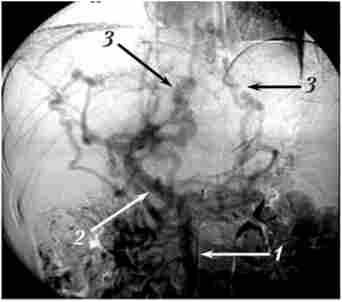

Найбільш інформативною виявляється дигитальная субтракційна артеріопортографія (рис. 17.6). Сутність методики полягає в катетеризації однієї з вісцеральних артерій стегнових доступом і реєстрації артеріальної і венозної фаз кровотоку. На флебограмм чітко візуалізуються воротная вена і основні її притоки, а також шляхи колатерального кровотоку з накопиченням контрастує речовини в венах стравоходу і склепіння шлунка.

Дигітальна субтракційна ангіограма

Мал. 17.6. Дигітальна субтракційна ангіограма.

Поворотна мезентерікопортографія: